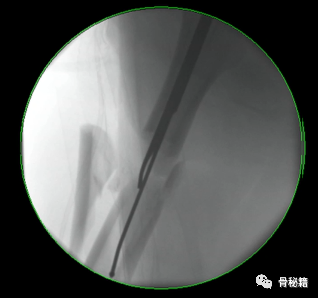

进针的角度,基本与股骨颈是垂直的角度

注意采用快钻慢进,用套筒来纠正方向。